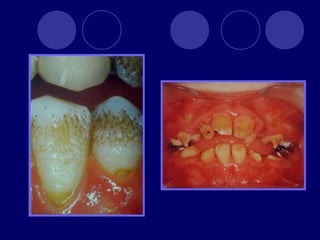

AMELOGENESIS IMPERFECTA  Hipoplásico: Zonas ausentes de esmalte  Afecta más a caras vestibulares  Esmalte: blanco amarillento y marrón claro, consistencia dura, fosas y surcos oscuras, delgado  Hipocalcificado:  Cualitativo  Esmalte frágil, fácil de desprender  Rx: falta de contacto entre dentina, esmalte  Hipomaduro:  Disminución en el contenido mineral  Esmalte blando y rugoso, veteado de blanco a marrón (esmalte en copos de nieve)  Más frecuente en caras vestibulares y dientes superiores

DISPLASIA AMBIENTAL DEL ESMALTE HIPOPLASIA POR INGESTA DE FLÚOR: fluorosis, manchas opacas, esmalte sin brillo(leve=lechoso, graves=amarillo/café) .